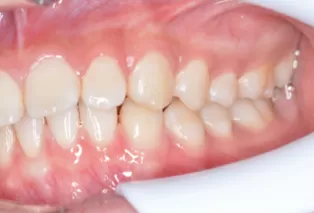

Intraoral photos after treatment